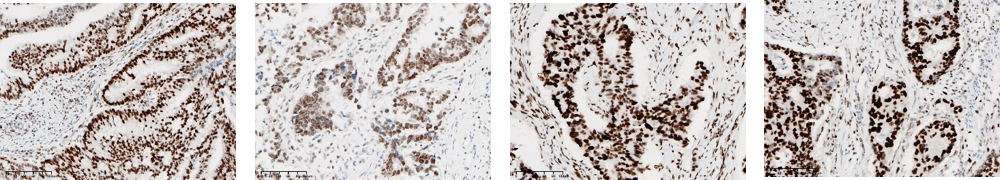

近日,熙寧生物|精翰生物參加中國(guó)非公立醫(yī)療機(jī)構(gòu)協(xié)會(huì)病理學(xué)專業(yè)委員會(huì)和國(guó)家病理質(zhì)控中心(PQCC)非公組聯(lián)合組織的特殊染色室間質(zhì)評(píng)活動(dòng),檢測(cè)指標(biāo)包括MSH2、MSH6、MLH1、PMS2、ER、PR、HER2、KI67、Claudin18.2、CD20、Bcl-2、Bcl-6、C-MYC、彈力纖維染色、粘液染色(AB[Ph2.5]法)、淀粉樣蛋白染色(剛果紅法),以上16項(xiàng)檢測(cè)指標(biāo)熙寧生物|精翰生物組織病理平臺(tái)均高分通過(guò),榮獲合格證書(shū)。

MLH1

MSH2

MSH6

PMS2

ER

PR

HER2

KI67